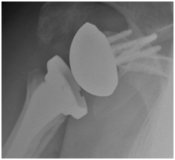

shoulder reverse shoulder replacement

X-ray of a reverse shoulder replacement